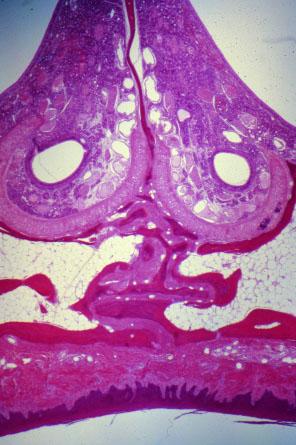

IX-2 (5) Slide 69, Nasal Septum (H&E). Hard palate (roof of the mouth, bottom) and nasal septum (top). The spaces on both sides of the septum are the nasal fossae.